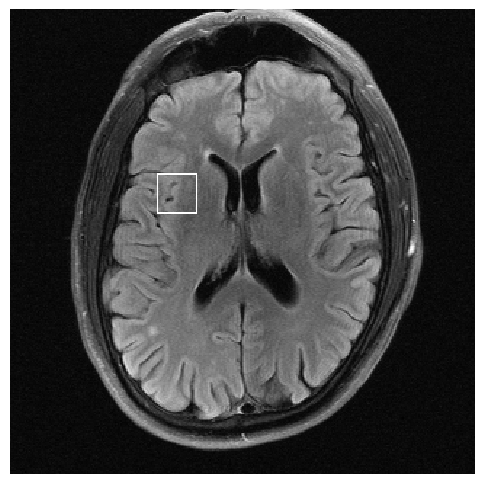

Figure 3: Reconstructions results. Rows 1 and 3: Examples of comparing the ground truth (GT) fully sampled image to the reconstructed images obtained by the three models (1-3), NPB-REC, baseline, E2E-VarNet trained with Dropout, and the NPB-REC std. map at accelerations R=4𝑅4R=4, R=8𝑅8R=8, respectively. Rows 2 and 4: The corresponding annotated ROIS of Nonspecific white matter lesions.

Fig. 3 presents examples of reconstruction results obtained by (1) our NPB-REC approach, (2) the baseline, and (3) Monte Carlo Dropout, for equispaced masks with two different acceleration rates R=4𝑅4R=4 and R=8𝑅8R=8. The reconstructed images predicted by the three models are smoother than the reference image. This is due to the fact that all the models were trained with SSIM loss, which tends to produce overly smooth reconstructions while preserving the diagnostic content and the anatomical features Sriram et al. (2020a). These images can be enhanced by dithering the image by adding a small amount of random Gaussian noise to produce a more textured reconstruction, as proposed in Sriram et al. (2020b).

Table 1 presents the mean PSNR and SSIM metrics, calculated over the whole inference set, for the three models. Our NPB-REC approach achieved significant improvements over the other methods in terms of PSNR and SSIM (Wilcoxon signed-rank test, pmuch-less-than\ll1e-4, except for SSIM values in line W, R=4𝑅4R=4 where they are roughly the same for NPB-REC and Baseline). The improvement in the reconstruction performance can be noted both quantitatively from the metrics, especially for masks with acceleration rate R=8𝑅8R=8, and qualitatively via the images of annotations, where our results show less smoothness than those obtained by Dropout.